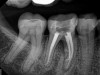

Fig 2. Tooth No. 14 was treated with silver points. In Figure 2, tooth No. 18 with mesial canals treated with Sargenti paste. The hallmark radiographic appearance of this technique is the light radiopacity within the canal system, as in Figure 3.

Figure 2

Fig 3. Tooth No. 14 was treated with silver points. In Figure 2, tooth No. 18 with mesial canals treated with Sargenti paste. The hallmark radiographic appearance of this technique is the light radiopacity within the canal system, as in Figure 3.

Figure 3